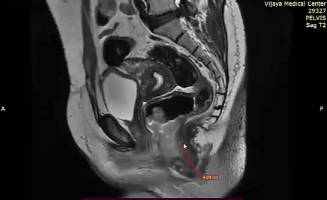

63 yo Anal T3

Large LN adjacent to tumor